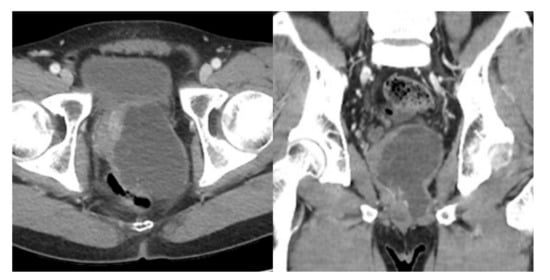

There were no complications postoperatively, and the patient was discharged on postoperative day 5. At the 12-month follow-up, computed tomography (CT) revealed the recurred mass in the previous surgical field, about 8.0 × 6.5 × 9.0 cm-sized, lobulated cystic lesion with multiple thin septa in the left prostate without solid component (Figure 3). Repeated laparoscopic complete resection of the mass was performed by dissecting the base of the cyst from the normal prostate tissue. The patient fully recovered after surgery without erectile dysfunction, urinary incontinence, and further recurrence.

Figure 3.

Abdominal CT showed an 8.0 × 6.5 × 9.0 cm-sized, lobulated cystic lesion with multiple thin septa in the left prostate without solid component.